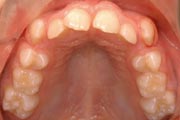

Crowding

After